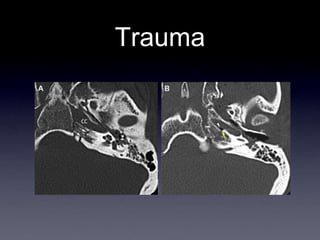

Trauma